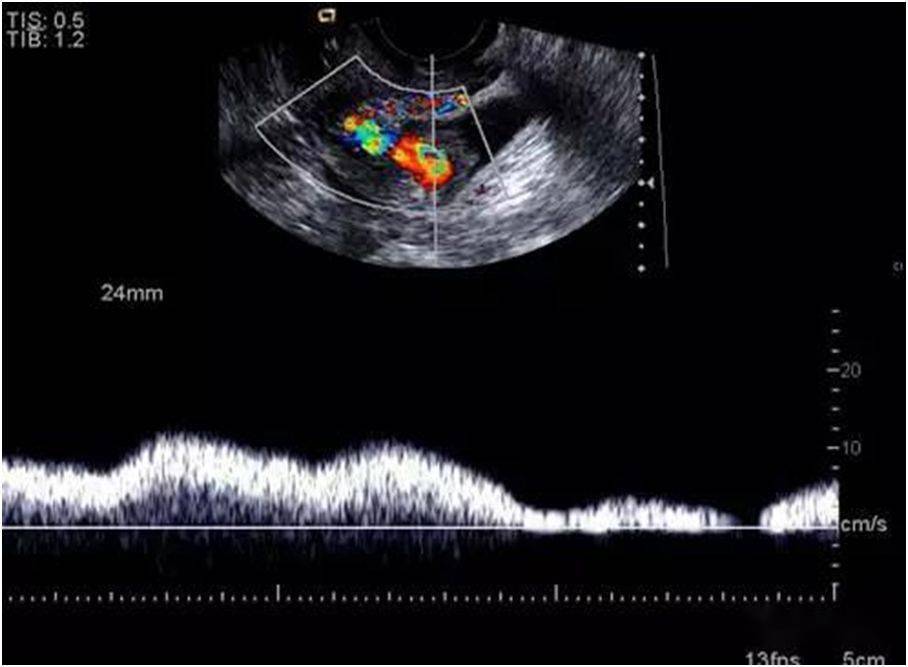

子宫穿孔超声表现图

子宫穿孔超声表现图,子宫穿孔超声图片

超声典型病例子宫穿孔

子宫穿孔的超声诊断

高手进阶:子宫穿孔的超声诊断

子宫穿孔彩超下表现

子宫穿孔彩超图